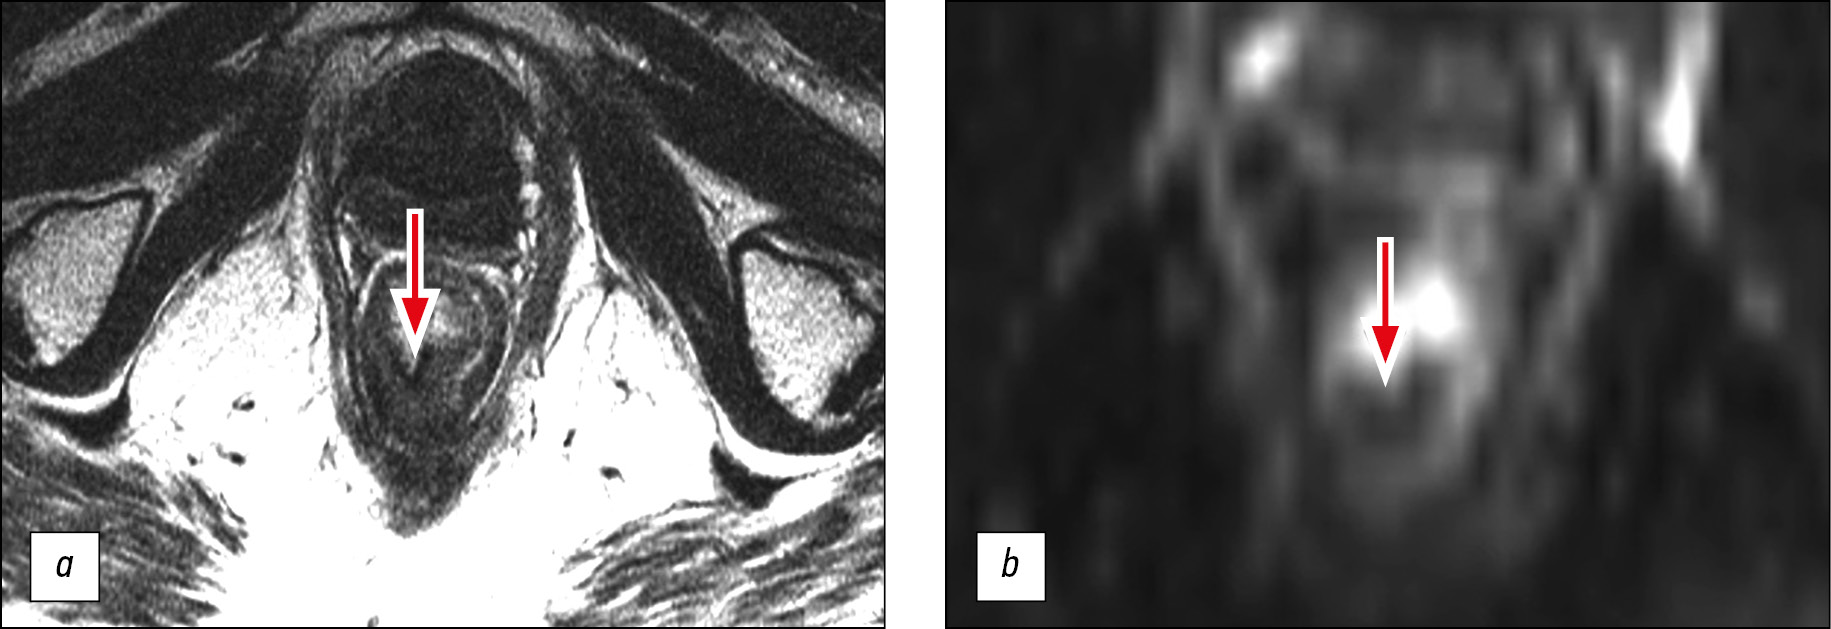

MRI was performed eight times throughout the 3-year follow-up, and the baseline MR image was obtained 1 month after the end of NHRT. This image was characterized by the replacement of the tumor located along the posterior semicircle of the rectum at a distance of 4 cm from the anal edge with a 1.5 cm-long thin fibrous scar that had no signs of diffusion limitation but had an increase in the initial coefficient (apparent diffusion coefficient, ADC) of up to 1.66 × 10−3 mm2/s. No suspicious lymph nodes were found in the mesorectum and near the pelvic walls. Therefore, the MR image corresponded to the tumor of the lower ampullar rectum (ymrT1-0N0), TRG2 (Fig. 2). The described MR image was retained without significant changes during the follow-up period.

Fig. 2. Magnetic resonance imaging of the tumor of the lower ampullar rectum 1 month after neoadjuvant chemoradiation therapy, ymrT1-0, TRG2: a ― T2-WI; b ― diffusion-weighted images. The tumor was replaced with a thin fibrous scar that had no signs of diffusion restriction (arrows).